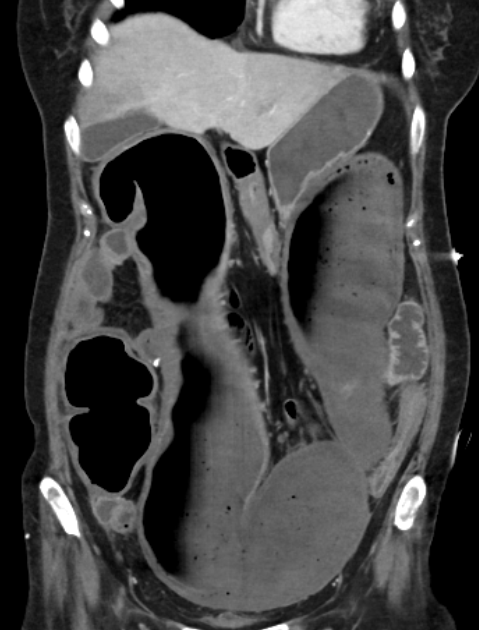

| 복부 X-Ray | 횡행결장 직경 > 6cm, 가스팽창, 장벽 얇아짐 |

| CT | 장벽 비후, 염증 확산, 청공 여부 확인 |